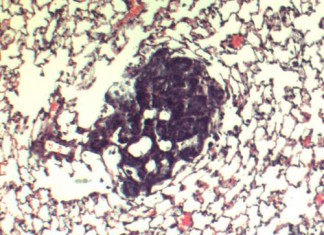

Vacuna biológica para la leishmaniasis humana

Una investigación ejecutado en la Universidad Autónoma de Yucatán (UADY) ha demostrado con éxito, en animales de ensayo, la eficacia de una vacuna que...